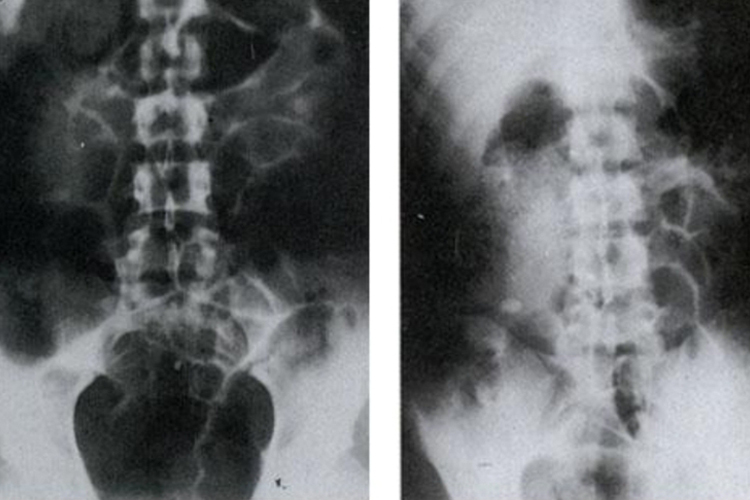

阑尾炎患者的腹部平片一般可见盲肠扩张和液气平面,偶尔可见钙化的肠石和异物影。

影像学检查一般包括腹部平片、超声和CT,阑尾炎患者进行影像学检查时,腹部平片可见盲肠扩张和液气平面,偶尔可见钙化的肠石和异物影,可帮助诊断。超声检查可发现肿大的阑尾或脓肿。CT的敏感性优于超声,尤其有助于阑尾周围脓肿的诊断。此外,阑尾炎的患者还可能会出现腹痛、厌食、呕吐、乏力等症状。